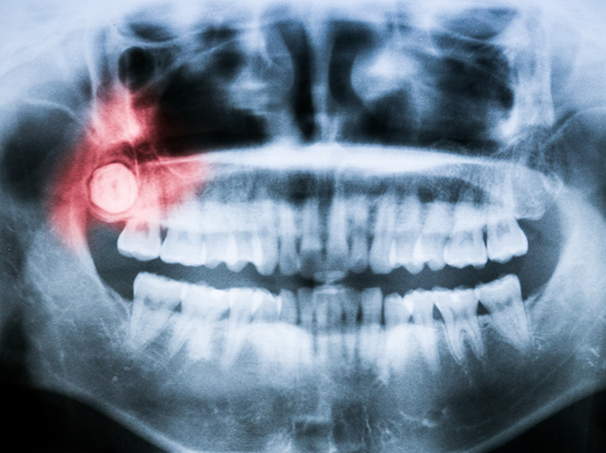

Wisdom teeth don’t always need to be extracted, but in the cases where they do, the process may require a surgical or simple extraction procedure. For wisdom teeth that are impacted below the gumline, our oral surgeon will need to gain access to the tooth or teeth by making a small incision in the gumline. From here, they can split the tooth or teeth up into smaller pieces to remove them from the mouth (this approach leads to a faster and easier recovery).